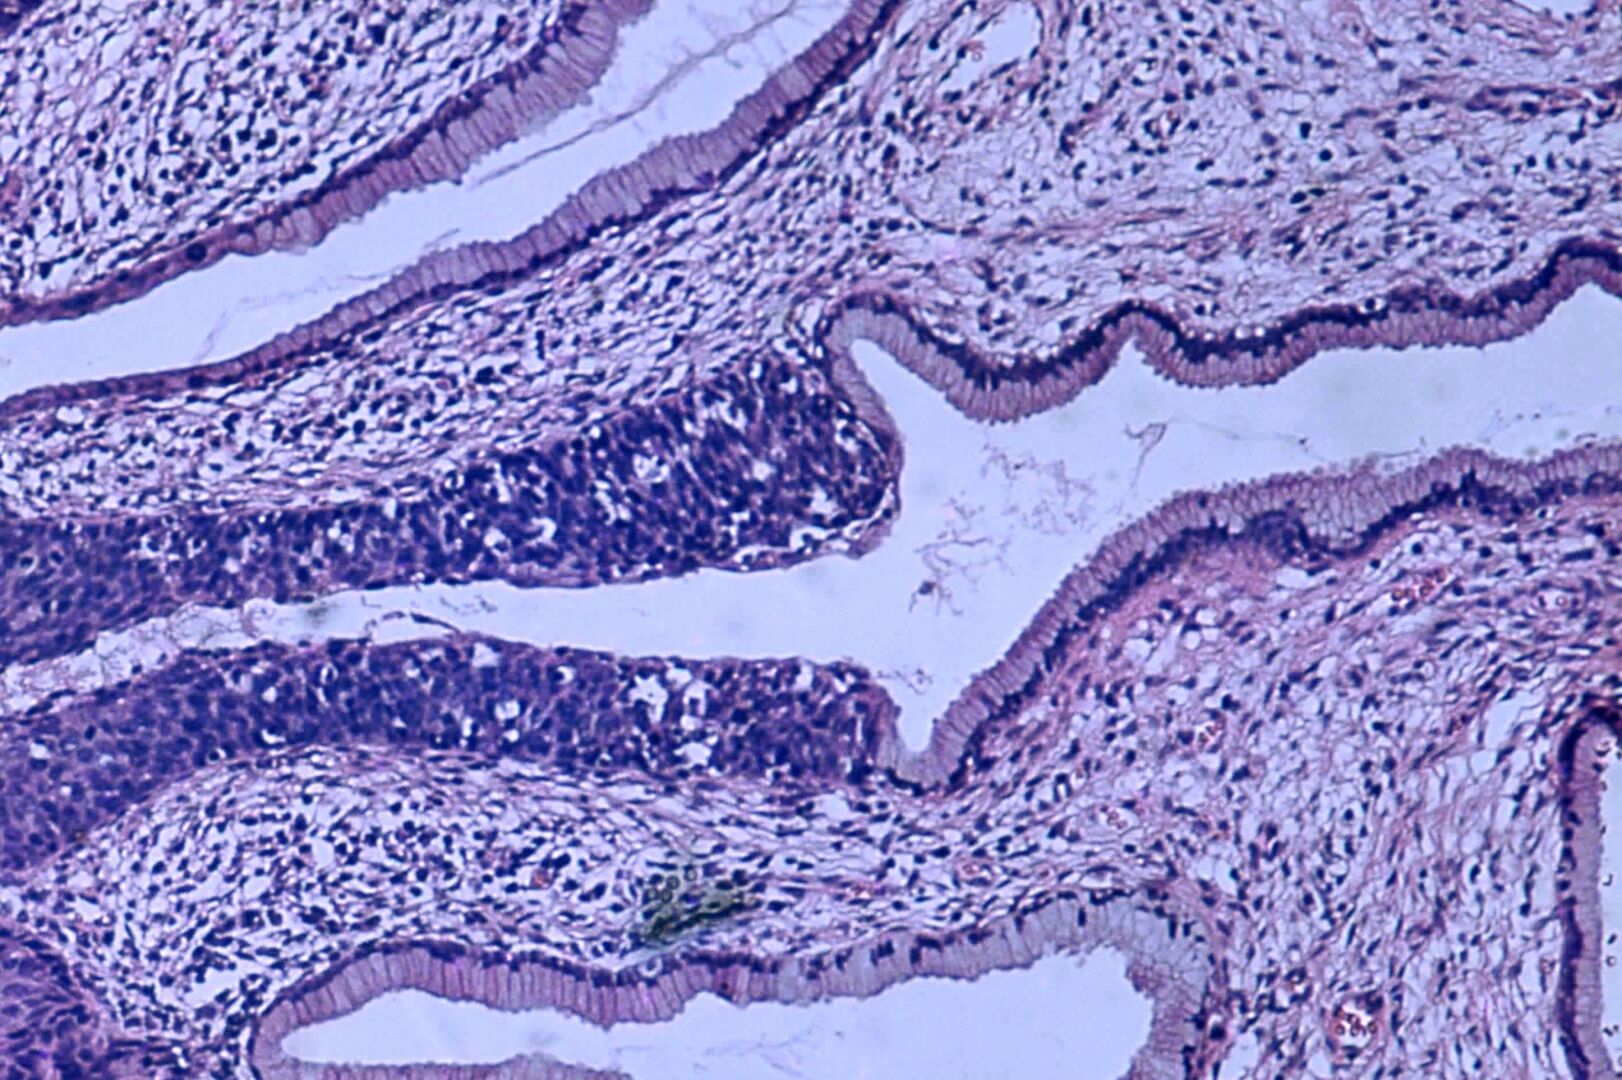

Эксперименты показали, что в зоне опухоли формируются анизотропные скопления наночастиц магнетита даже без внешнего магнитного поля. В комбинации с золотыми наночастицами эти агрегаты избирательно присоединяются к механорецепторам раковых клеток через аптамеры — искусственные нуклеотиды.

Сергей Карпов, ведущий специалист центра, пояснил: «Отдельные наночастицы магнетита неспособны активировать механорецепторы для запуска апоптоза. Однако моделирование броуновской динамики доказало, что частицы образуют анизотропные агрегаты без внешнего поля. Эти структуры формируются на золотых наночастицах, которые связываются с мембранами опухолей».